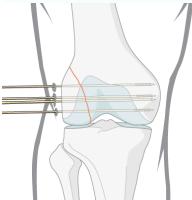

| ACL & PCL: Anterior/Posterior Drawer Test OR Lachman’s test OR Pivot Shift test | Assess integrity of Anterior and Posterior Cruciate Ligaments specifically | Anterior/Posterior Drawer Test: Lachman’s test: ![]() | Excessive anterior or posterior translation of the tibia, indicating ACL or PCL injury | |

| Meniscus: McMurry’s test OR Medial & Lateral joint tenderness Apley grinding test | Assess for meniscal tears | McMurry’s test: Apley grinding test: ![]() | Click, thud, or pain during knee flexion, extension, and rotation during McMurray’s; pain during compression and rotation during Apley’s. | |